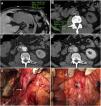

Cortes axiales del mismo paciente del vídeo 2. Tomografía computarizada basal (A) y en fases arterial (B) y portal (C) que demuestra pérdida del plano graso de separación (*) entre el injerto y la tercera porción duodenal (d) con extravasación activa de contraste intravenoso hacia la luz duodenal evidente desde la fase arterial. Reconstrucción en el plano coronal (D).

Fístula aortoduodenal primaria en varón de 90 años con hematemesis y dolor abdominal intenso en contexto de síndrome aórtico agudo. La tomografía computarizada (TC) basal muestra un gran coágulo de 40 UH en el estómago (A) y un aneurisma aórtico calcificado (a) con pérdida del plano graso de separación con la luz duodenal (d) (B). La TC con contraste intravenoso (CIV) en fase arterial (C) muestra una úlcera penetrante (flecha) y extravasación activa de CIV (punta de flecha) hacia el duodeno. Las reconstrucciones MIP en planos coronal (D) y sagital (E) muestran el flap intimomedial (flecha) y el jet de CIV (punta de flecha).

Fístula aortoentérica secundaria en varón de 77 años con antecedente de bypass aortobifemoral que actualmente presenta episodio de sangrado gastrointestinal con hematoquecia masiva, distensión abdominal y pulsos distales débiles. La tomografía computarizada basal (A), en fases arterial (B), portal (C) y la reconstrucción sagital MIP (D) muestran un desgarro intimomedial (flecha) que afecta a la superficie anterior del injerto contactando con la tercera porción del duodeno (d). Se observa asimismo extravasación del contraste aórtico al tracto gastrointestinal (punta de flecha).